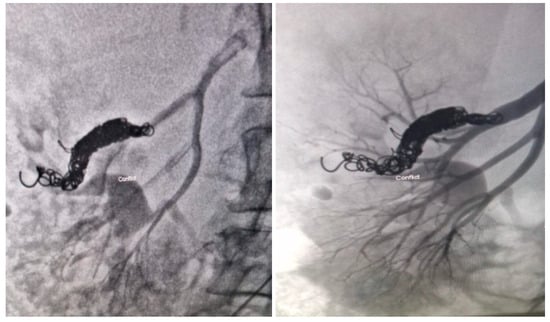

Appendix A.1. Clinical Case 1: Right Renal Visceral Arteriovenous Malformation